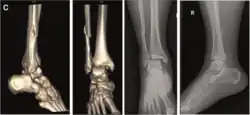

| Pronation-Abduction |

|

![]() |